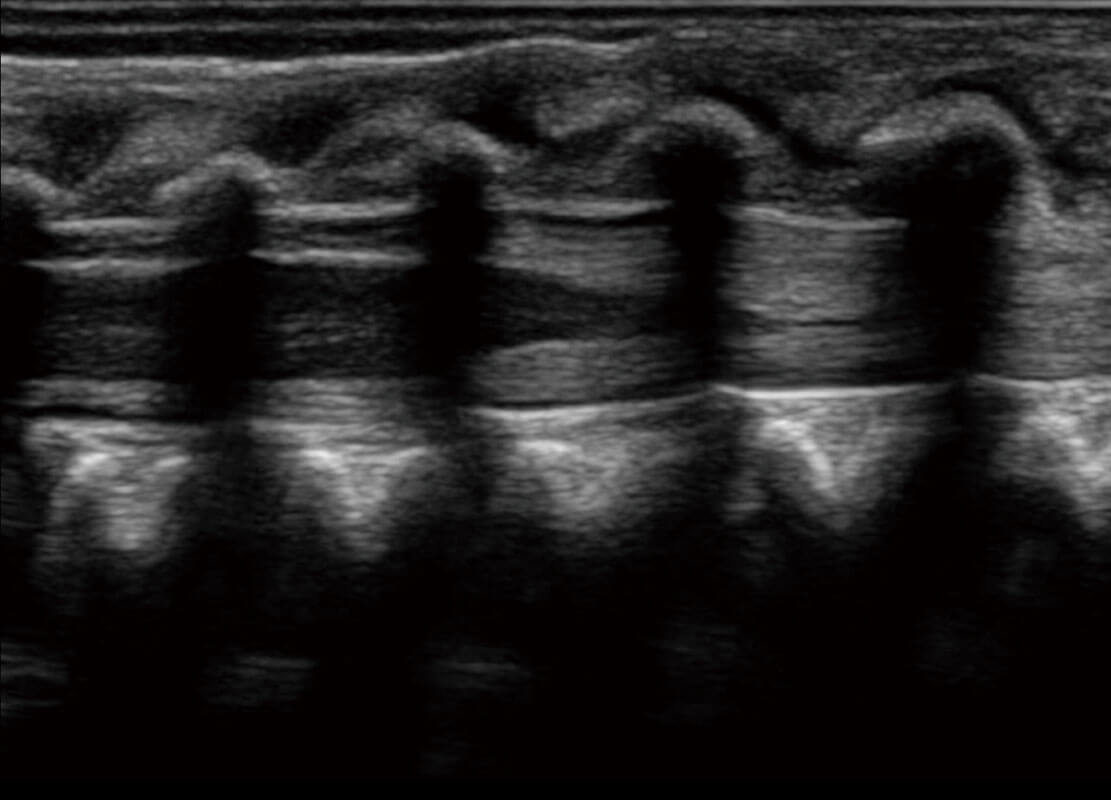

四腔切面

P60搭载一系列胎儿心脏成像技术,实现精细的胎儿心脏评估。